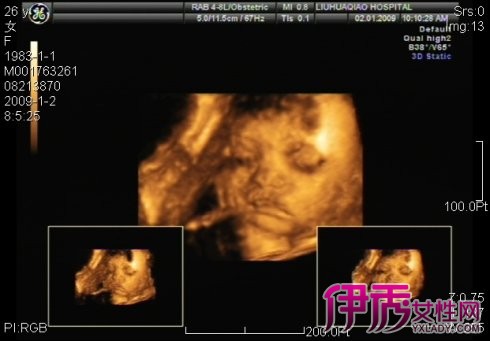

由于组织结构与液体灰阶反差较大,可清晰显示可疑结构的立体形态、表面特征、空间位置关系,提供胎儿在宫内的立体图像。三维重建包括表面成像、透明成像及多平面成像模式。

三维彩超表面成像用于产科检查,不仅可观察到胎儿成长的过程,而且可以检查胎盘、羊水及脐带的变化,更重要的是可作为诊断胎儿畸形的主要手段。由于组织结构与液体灰阶反差较大,可清晰显示可疑结构的立体形态、表面特征、空间位置关系,提供胎儿在宫内的立体图像。三维重建包括表面成像、透明成像及多平面成像模式。其优点是:

(3)立体显像,动态直观;可实时动态观察胎儿头部、躯体表面及内脏活动,图像清晰精确可靠。

(7)可显示不同层次病灶的立体关系及毗邻关系。三维彩超在产科的应用为临床超声诊断提供了丰富的影像信息,胎儿在羊膜腔内被液体包绕是三维超声良好的成像条件,图像立体、形象直观,可任意调整角度,通过三个切面的旋转可观察到可疑结构,对胎儿大体结构的畸形可一目了然,极大地提高了诊疗质量,减少了误诊或漏诊。

孕妇三维彩超图片